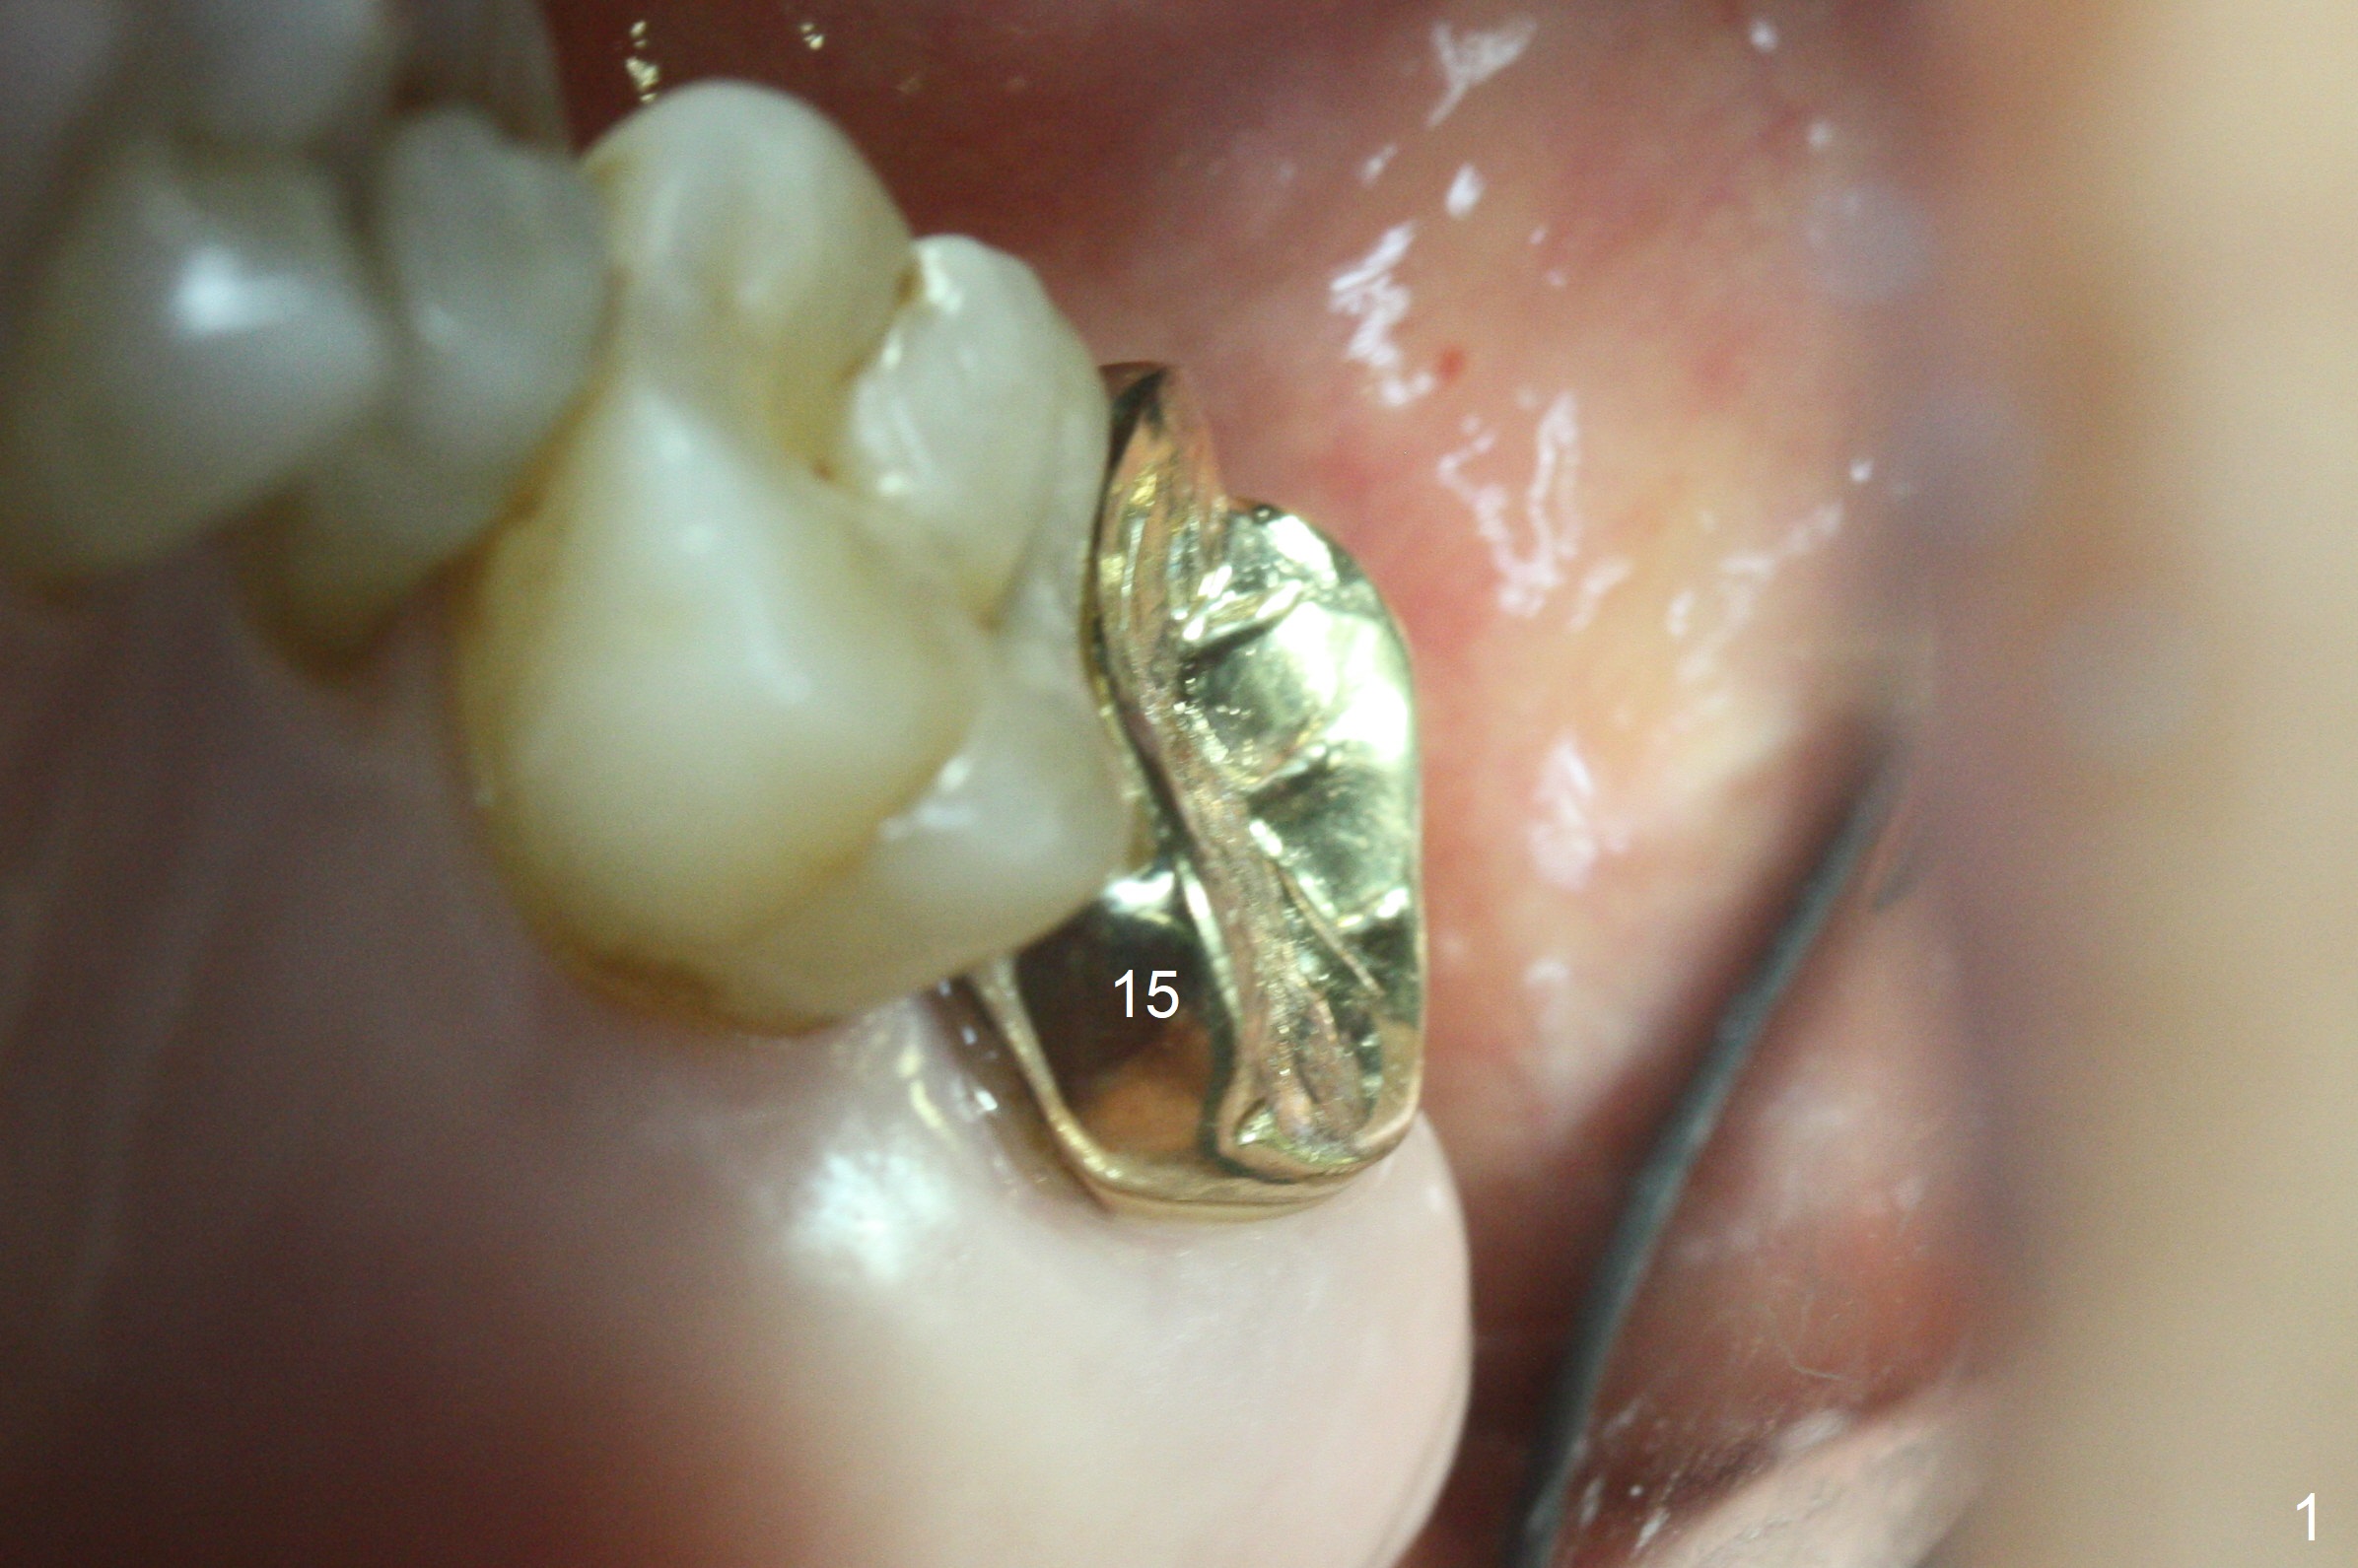

Extraction of the tooth #15 with short clinical crown (suggesting bruxism, Fig.1) reveals a vertical root fracture (Fig.2 <). It seems unnecessary and difficult to create osteotomy in the mesial slope. What can be done is to place starter and 2 mm drills as mesial as possible (Fig.3 (red dashed line: sinus floor). After use of Lindamann bur to move the osteotomy mesially and sequential osteotomy until 3.8x18 mm, a 4.5 mm tap is inserted with clearance from the impacted tooth #16 (Fig.4). A 5x15 mm implant is placed with >60 Ncm with clearance from the 3rd molar (Fig.5,6). If the impacted tooth were removed, the primary stability is expected to be reduced. Impression is taken 6 months postop with 19/20 implants (Fig.7). The bone graft remains in the crestal area immediately and 11 months post cementation (Fig.8,9 *). In the other word, new crestal bone forms after extraction.